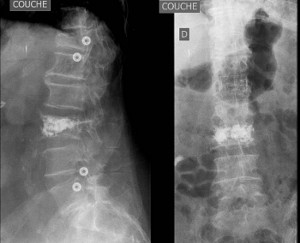

- Sagittal correction after short percutaneous fixation for thoracolumbar compression fractures: comparison of the combination of SpineJack® kyphoplasty and fractured vertebra screw fixation. Finoco M, Dejean C, Giber D, Bastard C, Ferrero E, Dubory A, Khalifé M. Int Orthop. 2023 May; doi: 10.1007/s00264-023-05734-9

- Implant removal after short percutaneous pedicle fixation associated with SpineJack® kyphoplasty: is correction sustained? o Finoco M, Dejean C, Giber D, Ferrero E, Khalifé M. o Trauma Surg. 2023 Jul;143(7):4239-4247. doi: 10.1007/s00402-022-04726-5.

- Risk factors of instrumentation failure and pseudarthrosis after stand-alone L5-S1 anterior lumbar interbody fusion: a retrospective cohort study o Antoine Jaeger MD David Giber MD Claire Bastard MD; Benjamin Thiebault MD; Arnaurd Dubory MD PhD; Charles-Henri Fouzat-Lachaniette MD PhD. o Journal of neurosurgery: spine